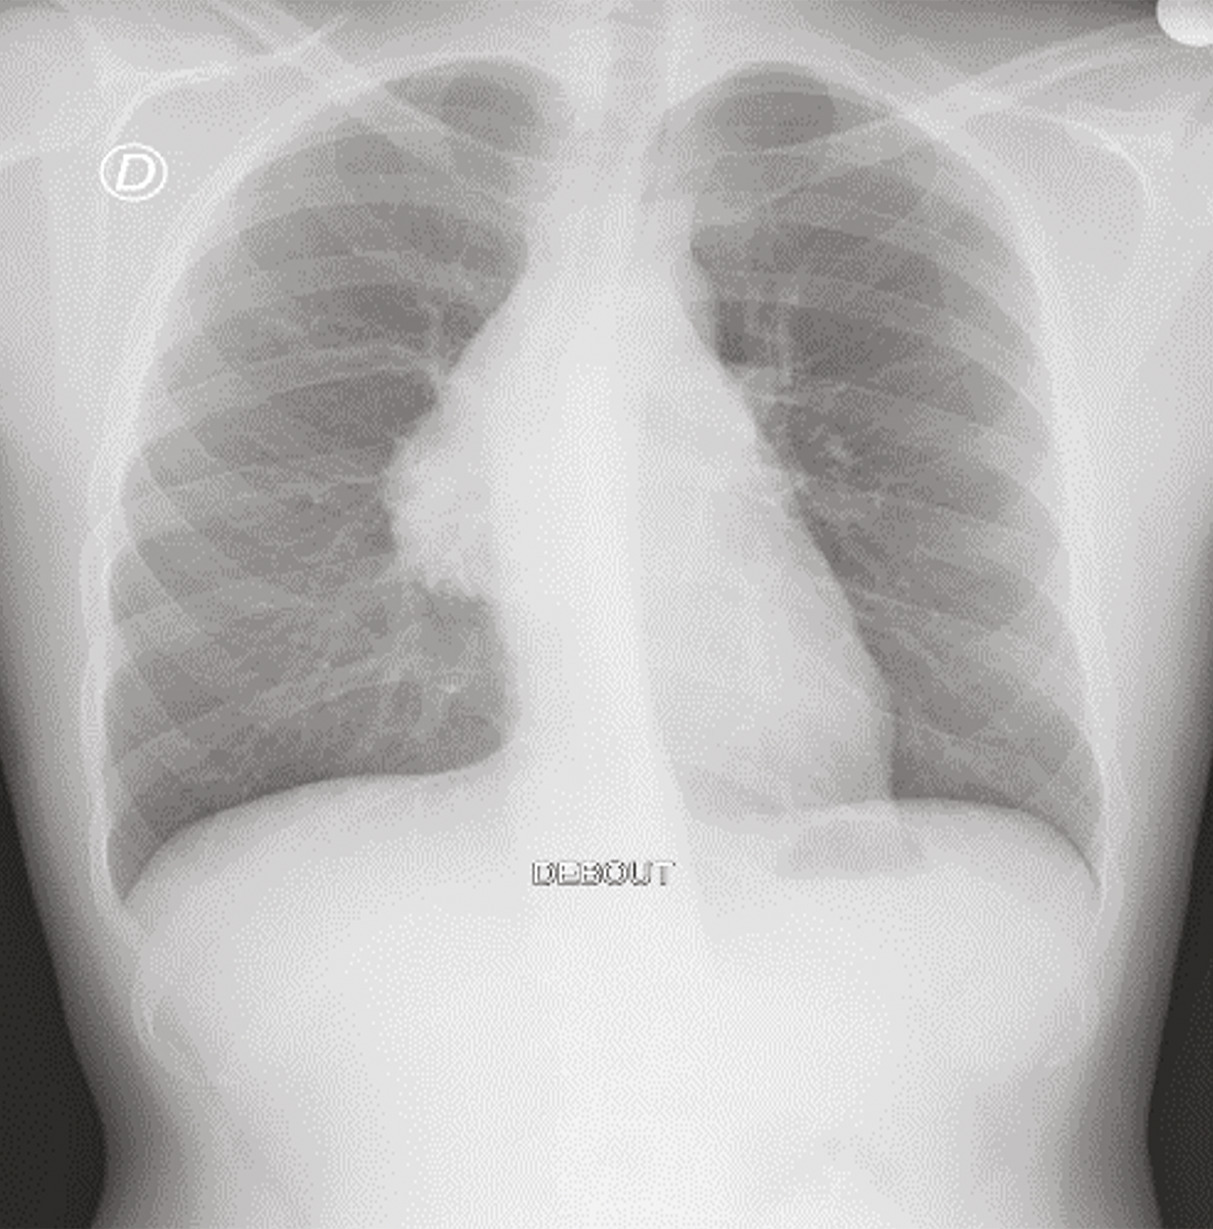

Le bilan biologique n’a pas montré de syndrome inflammatoire (hémogramme, protéine C réactive [CRP] et vitesse de sédimentation [VS] normaux). Les radiographies standard du bassin et du rachis lombaire, de même que l’échographie des hanches, étaient sans particularité. Mais la radiographie pulmonaire de face a mis en évidence une opacité médiastinale parahilaire droite se raccordant en pente douce avec le médiastin ainsi qu’une interface nette avec le poumon, évoquant une tumeur médiastinale (fig. 1).

Un complément scanographique a montré la présence d’une masse du médiastin antérosupérieur, de forme ovalaire, mesurant 10 × 9,5 cm, de contours réguliers et nets, et se réhaussant de manière hétérogène après injection du produit de contraste. Une adénopathie médiastinale y était associée avec la même densité, sans autre anomalie pleuropulmonaire (fig. 2).